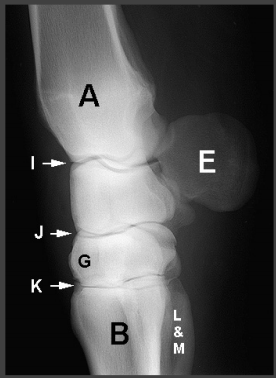

Carpus:

A - Radius

I - Antebrachiocarpal joint

E - Accessory carpal bone

J - Middle carpal joint

G - Third carpal bone

K - Carpometacarpal joint

B - Third metacarpal bone

L - Second metacarpal bone

M - Fourth metacarpal bone